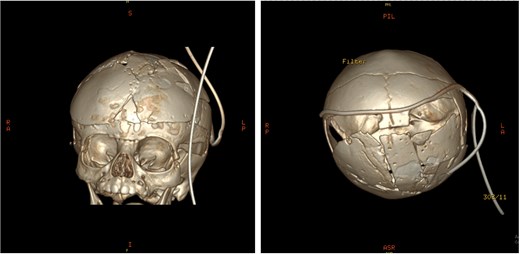

An 11-month-old female infant, born to unrelated Saudi parents, was referred to our facility with unilateral left coronal craniosynostosis, congenital microcephaly, global developmental delay, and a confirmed ZIC1 gene mutation. Comorbidities included a patent foramen ovale, aortopulmonary collateral vessel, G6PD deficiency, and gastroesophageal reflux disease (GERD). At birth head circumference was 29 cm (<first percentile), and progressive skull asymmetry and squinting were noted over time. Developmentally, she exhibited delayed gross and fine motor skills with limited object transfer. On examination, she was alert and visually tracking, with inward ocular deviation (esotropia). Head circumference was 37 cm (<first percentile) with anterior plagiocephaly and towering of the left frontal region (Fig. 1). Pupils were equal and reactive. Fundoscopy and cranial nerve examinations were unremarkable. Gross motor power was within normal limits, except for moderate lower limb spasticity. 3D reconstruction computed tomography (CT) confirmed premature fusion of the left coronal suture with subtle elevation of the superolateral orbital rim, indicating harlequin sign (Fig. 1). Brain CT showed corpus callosum agenesis, colpocephaly, mild ventriculomegaly, right cerebellar and pontine hypoplasia, and a large cisterna magna, consistent with the reported ZIC1-related malformation spectrum (Fig. 2). Given the progressive deformity and concerns of increased intracranial pressure that might be partially contributing to her neurodevelopmental delay, anterior cranial vault expansion with fronto-orbital advancement was performed jointly by the neurosurgery and plastic craniofacial teams (Fig. 3). Intraoperatively, left-sided dural tension was appreciated, indicating localized increased intracranial pressure. The orbital bandeau was reshaped and advanced, achieving immediate cosmetic improvement (Fig. 4). The patient tolerated the surgery well and recovered uneventfully. At her 4-month follow-up, she showed developmental progress including standing without support, purposeful hand use, and verbalization (“Baba”). At 6-month follow-up, brain CT revealed areas of bone resorption which led to the placement of a ventriculo-peritoneal shunt (Fig. 5). The known association of ZIC1 mutation with tethering of the cord prompted spinal magnetic resonance imaging (MRI) screening. Positive findings indicated an untethering procedure, which was successfully done (Fig. 6).

Pre-operative 3D reconstruction CT showing left plagiocephaly with towering, and a subtle harlequin sign.